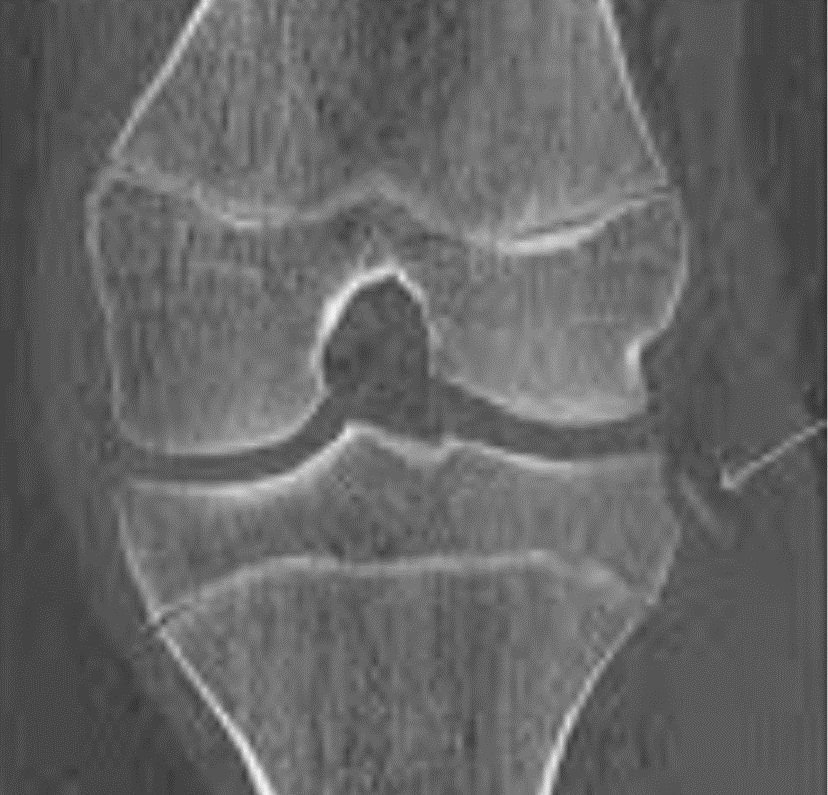

Fractura de estrés del metatarsiano: biomecánica y prevención

La fractura de estrés del metatarsiano es una lesión por sobrecarga frecuente en deportistas, militares y cualquier persona sometida a un aumento brusco de la carga de impacto sobre el pie, y su incidencia ha crecido de forma paralela al auge del running y los deportes de alta demanda física. A diferencia de las fracturas […]